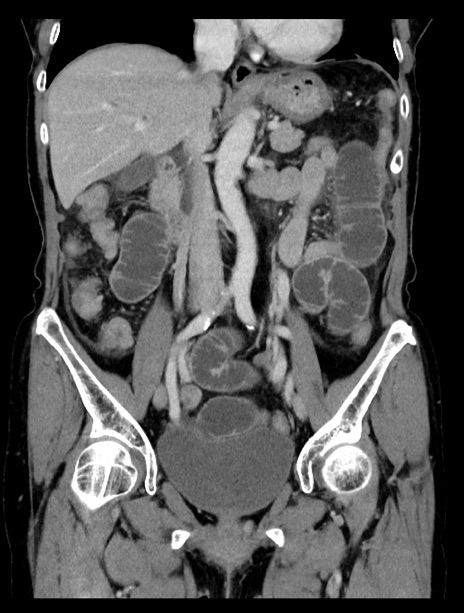

症例23(冠状断像)

【症例】70歳代女性

【主訴】下腹部痛・嘔吐

【現病歴】2日前より腹痛あり。昨日嘔吐あり。症状改善しないため来院。

【既往歴】胃GISTに対して胃部分切除後。

【身体所見】BT 37.1℃、BP 128/77mmHg、腹部:平坦・軟、下腹部に圧痛あり。

【データ】WBC 10200、CRP 0.31